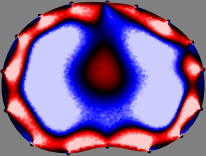

To explain the FER method, we closely examine the correlations among column vectors of the sensitivity matrix , described in Fig. 2. The correlation between and can be expressed as

for [23]. This shows that the column vector is like an EEG (electroencephalography) data induced by dipole sources with directions at locations . Given that two dipole sources at distant locations produce mutually independent data, the correlation between and decreases with the distance between and . Fig. 2 shows a few images of the correlation as a function of for four different positions . The correlation decreases rapidly as the distance increases. In the green regions where the correlation is almost zero, is nearly orthogonal to .

Fig. 2 shows that if and are far from each other, the corresponding columns of the sensitivity matrix are nearly orthogonal. This somewhat orthogonal structure of the sensitivity matrix motivates an algebraic formula that directly computes the local ensemble average of conductivity changes at each point using the inner product between changes in the data and a scaled sensitivity vector at that point: